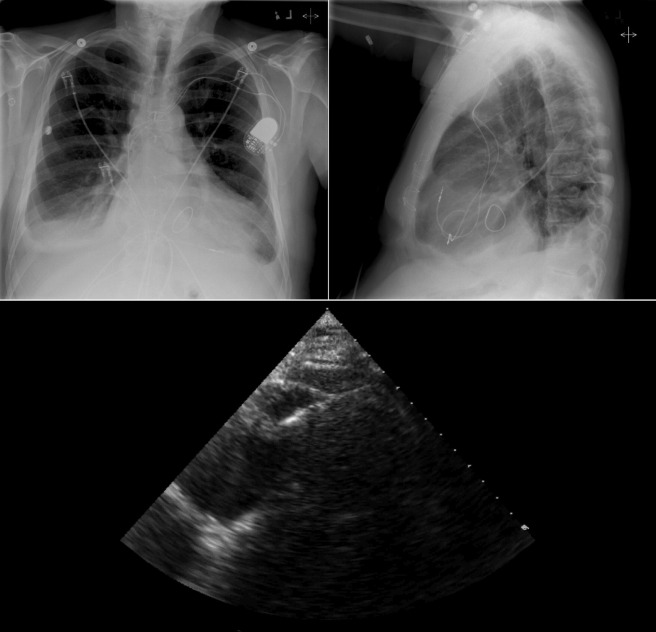

Chest radiography has a standard role in the identification of several potential complications such as pneumothorax, hemothorax, and several forms of malposition after insertion of pacemakers, implantable cardioverter defibrillators (ICDs), and cardiac resynchronization therapy devices.

Pacemaker leads are apparent, and ICDs are more obvious because of their larger coils. Coronary sinus leads for cardiac resynchronization therapy are finer leads.

Endocardial Pacer Leads

The position and integrity of endocardial pacer leads should be verified, especially when pacemaker dysfunction is clinically suspected ( Graphics 23-1 to 23-4 ; Figs. 23-1 to 23-15 ).The most common cause of pacemaker dysfunction that is apparent on the chest radiography is distal lead displacement/misplacement.

With a right atrial lead , the tip should be in the right atrial appendage.

With a right ventricular lead , the tip should lie anteriorly at the apex of the heart.